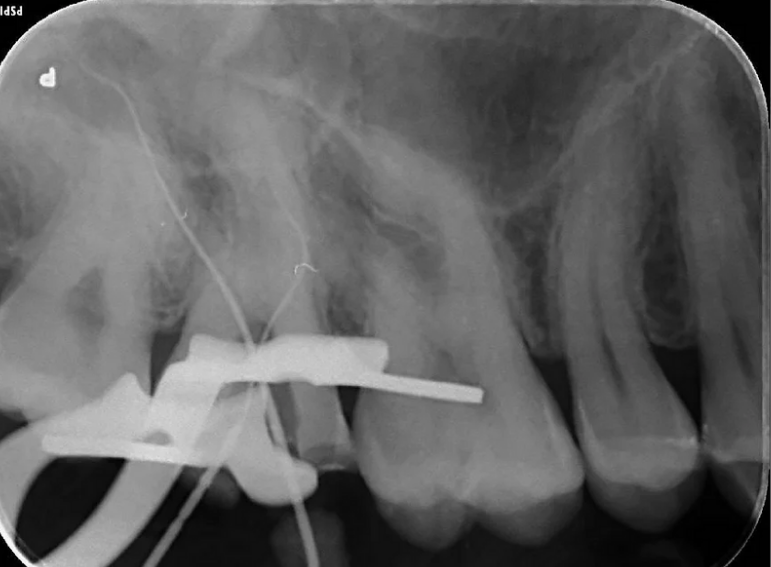

Separated instrument management on a sclerosed upper second molar.